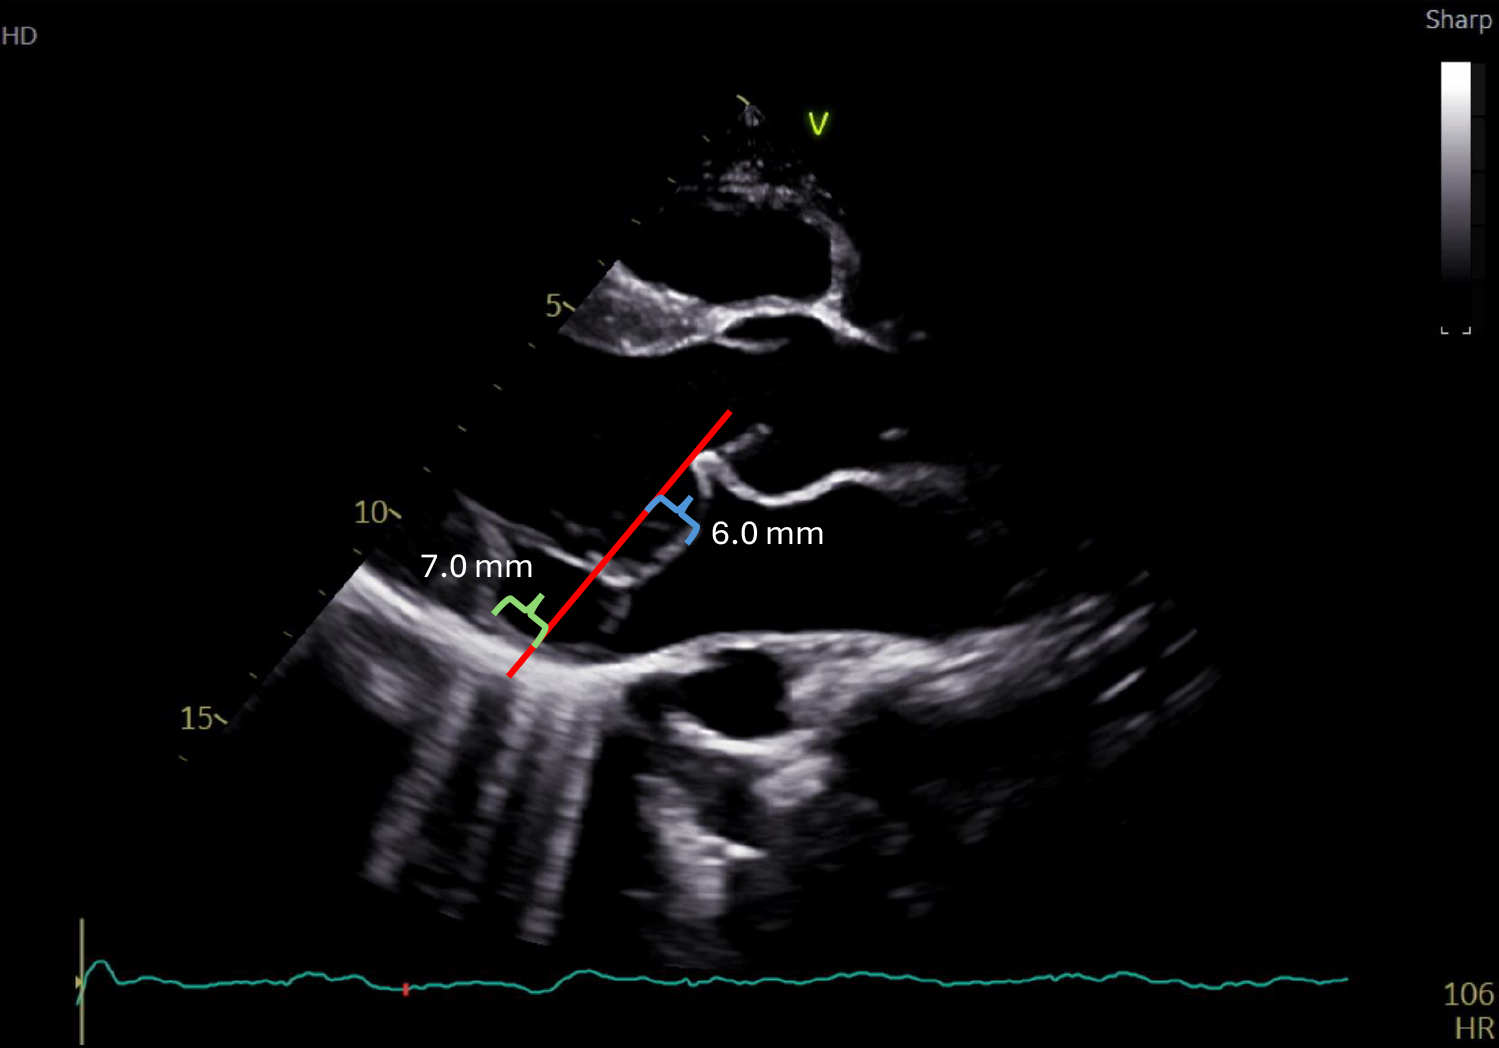

Figure 2: Systolic Frame From the Echocardiogram in Video 1 Showing a PLAX View

There is MVP with displacement of the MV leaflets 6 mm (blue bracket) from the plane of the MV annulus (red line). There is also a separation of the mitral annulus and LA wall from the LV myocardium of approximately 7 mm (green bracket), consistent with MAD.

LA = left atrial; LV = left ventricular; MAD = mitral annular disjunction; MV = mitral valve; MVP = mitral valve prolapse; PLAX = parasternal long-axis.